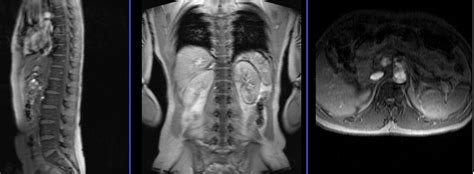

Uses of MRI Scans | Cogniflex Review

Uses of MRI Scans | Cogniflex Review from cogniflexreview.com

How Long Does MRI Take for full Body? - InNewsWeekly

How Long Does MRI Take for full Body? - InNewsWeekly from innewsweekly.com